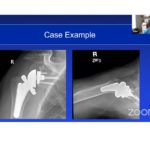

Revision Shoulder Arthroplasty

Courtesy: Robert Hudek MD, Shoulder and Elbow Surgeon, ATOS Clinic, Hamburg, Germany